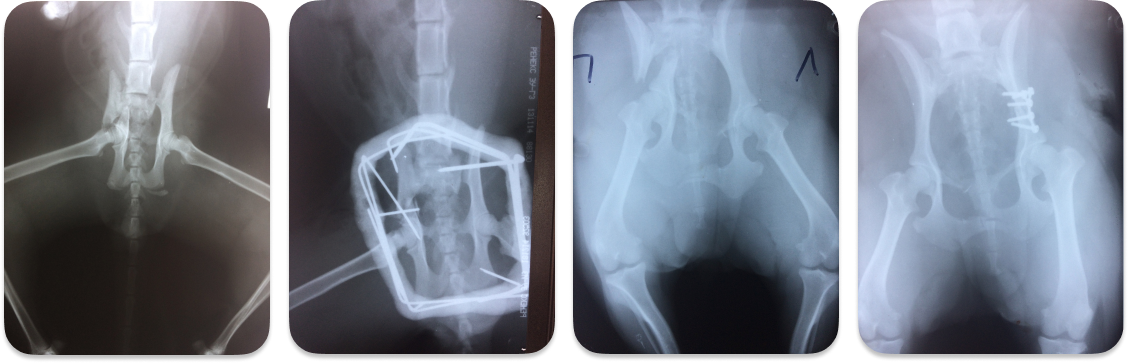

Перелом таза у собаки

Перелом таза у собаки 139 фотографий